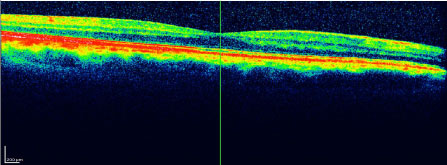

A 58-year-old man has been examined for the first time on 2012.09.28. Discovery of numerous drusen on the ocular fundus. Confirmation is made by O.C.T (Figure1 and Figure 2). A prescription of alimentary complement is seriously advised to the patient. The patient is at new consulted on 2013.09.26 after taking each day one tablet of alimentary complement. The control with O.C.T. shows an important regression of the drusen (Figures 3 and Figure 4). The prescription of alimentary complements has been maintained and observed by the patient which has been consulted in September 2014 (Figure 5, Figure6, Figure 7 and Figure 8) and 2015.09.24 (Figure 9, Figure 10, Figure11 and Figure12). We note that the central drusen are not reappeared, but the peripheric drusen persist.

Figure 1: OCT right retina on 2012.9.28 before treatment by alimentary complementation. View Figure 1

Figure 2: OCT left retina on 2012.9.28 before treatment by alimentary complementation. View Figure 2